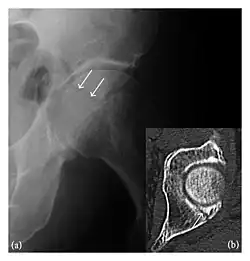

Occult osseous injuries may result from a direct blow to the bone by compressive forces of adjacent bones against one another or by traction forces during an avulsion injury. Lesions in the tibial plateau, hip, ankle, and wrist are often missed. In a tibial plateau fracture, any disruption of the posterior and anterior cortical rims of the plateau should be sought. Impaction of subchondral bone will appear as an increased sclerosis of the subchondral bone (Figure 1). In the hip, posterior acetabular fractures also present subtle radiographic findings. The acetabular lines should then be carefully examined keeping in mind that the posterior rim, which is harder to see on X-rays, is more frequently fractured than the anterior rim (Figure 2). In the wrist, detection of carpal bone fractures is often challenging, with up to 18% of scaphoid fractures radiographically occult. Carpal fractures, especially the scaphoid, are associated with the risk of avascular necrosis. In apparently normal wrist radiographs from symptomatic patients, if there is history of a fall on an outstretched hand with pain in the anatomic snuffbox, suggesting scaphoid injury, the initial examination with posteroanterior, lateral, and pronation oblique views must be complemented by other specific views such as supination oblique and the "scaphoid" view A careful examination of cortices for evidence of discontinuity or offset and cancellous bone for lucency is necessary (Figure 3).[1]

Figure 4: Dorsal triquetral fracture of the left wrist in a 30-year-old man after a trauma. (a) Anteroposterior radiograph shows a normal appearance. (b) Lateral radiograph of the same wrist demonstrates a chip fracture off the dorsal aspect of the triquetrum (arrow).[1]

Figure 6: Subtle anterior talar fracture in a 39-year-old man presenting with ankle pain after a fall. (a) Anteroposterior radiograph shows a subtle oblique radiolucent line through the talus (white arrows). (b) Sagittal CT reformation confirms the presence of an anterior talar fracture with cortical offset (black arrow). Avulsion fractures, which consist of a detached bone fragment resulting from a ligament or tendon pulling away from the bone, may also present with subtle radiographic signs. Tiny osseous fragments near the presumed attachment site of a ligament suggest this diagnosis. Common sites are the lateral tibial plateau (the Segond fracture), the spinal tuberosity of the tibia resulting from anterior cruciate ligament avulsion, and the ischial tuberosity.[1]